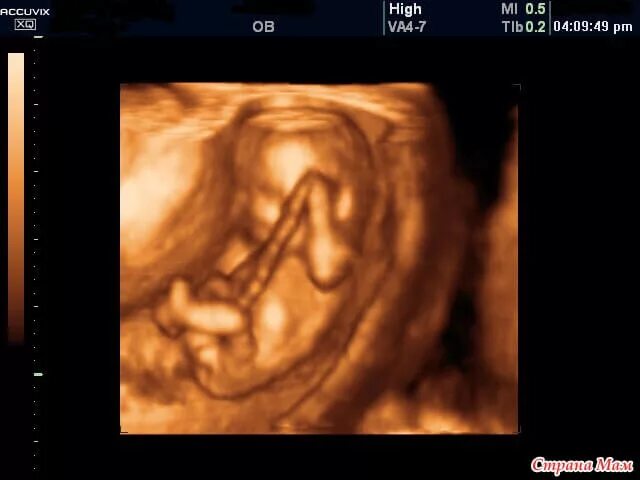

10 неделя пол ребенка